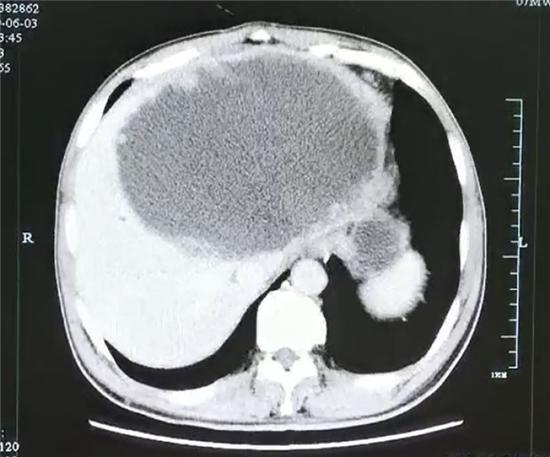

引流前肝脏巨大脓肿,壁厚,且壁上见很多肿瘤样的结构。

入院后,腹部CT检查发现肝脓肿壁上长了很多肿瘤样的结构,而且壁很厚,看来这个肝脓肿不简单。